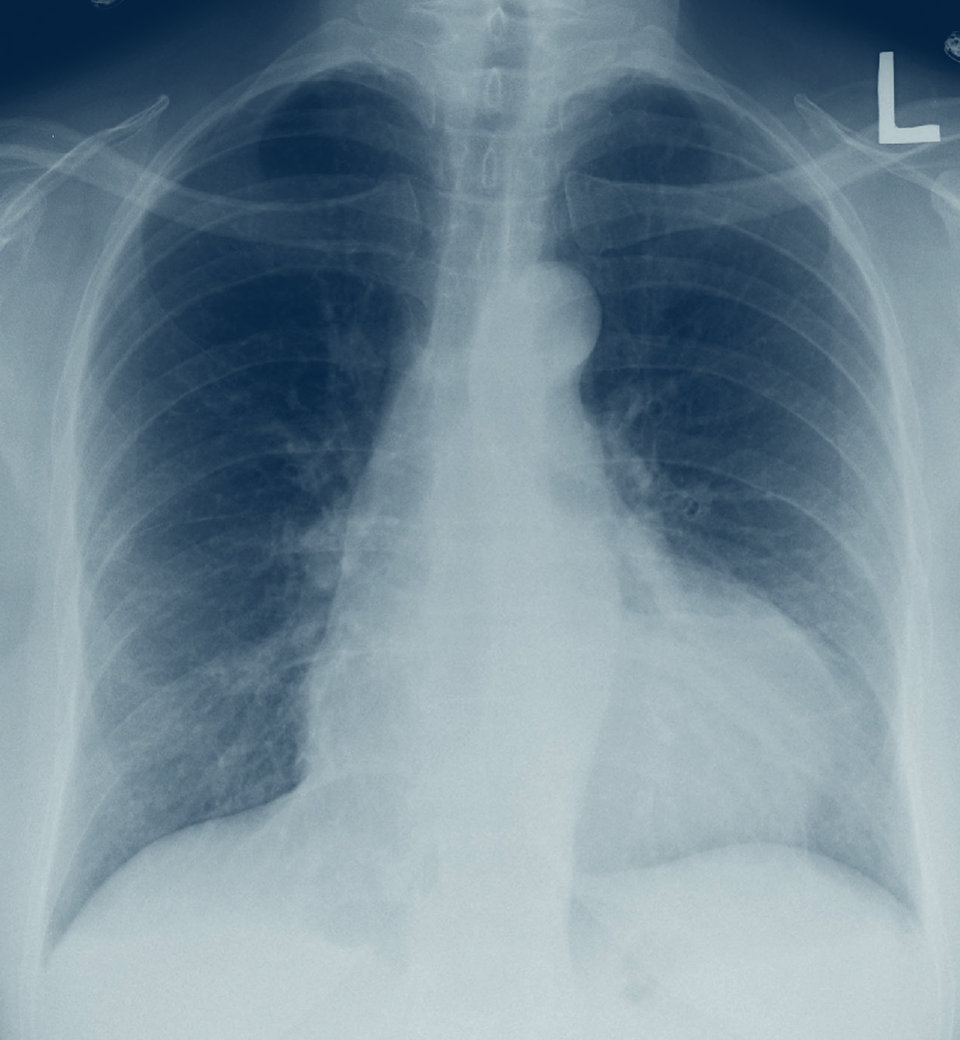

Ein großer Perikarderguss hat das Herz radiologisch stark vergrößert.

© wikimedia/James Heilmann. Ein großer Perikarderguss hat das Herz radiologisch stark vergrößert. © wikimedia/James Heilmann.